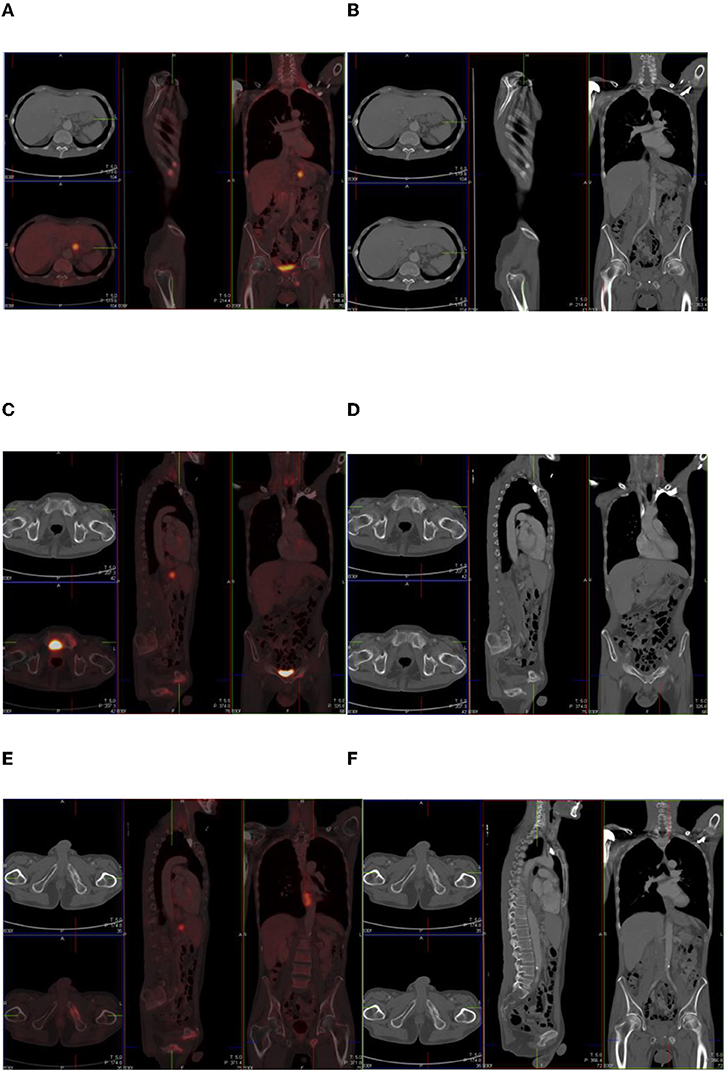

Agonistas GLP-1, como semaglutida e liraglutida, influenciam o metabolismo da glicose e o sistema nervoso simpático, resultando numa distribuição atípica de radiomarcadores. Os estudos indicam um aumento na acumulação do fármaco em músculos, coração e tecido adiposo marrom — um efeito que pode ser erroneamente interpretado como um tumor ou inflamação.

Os autores destacam que a ausência de diretrizes nacionais e internacionais para a interpretação desses exames pode levar a diagnósticos incorretos, procedimentos desnecessários e ansiedade para os pacientes. Em vez de suspender a terapia, eles recomendam que os radiologistas considerem o histórico de uso de medicamentos GLP-1 ao analisar os resultados de PET-CT.